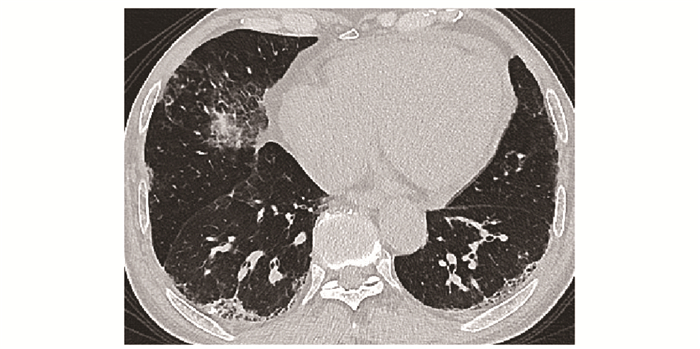

• 摘要: 结缔组织病累及呼吸系统可表现为间质性肺疾病、弥漫性肺泡损伤、肺泡出血、肺血管病变、胸膜病变及气道病变等。其临床表现缺乏特异性, 肺功能和胸部CT是最常用的检查手段。不同结缔组织病累及呼吸系统的影像特征具有相似性, 但又各具特点。本文就结缔组织病呼吸系统受累相关影像表现进行概述, 以提升读者的认知并指导临床实践。

Abstract: Respiratory manifestations of connective tissue diseases include interstitial lung diseases, diffuse alveolar injury, alveolar hemorrhage, pulmonary vascular lesions, pleural lesions and airway disease. Their clinical symptoms were not specific. Pulmonary function test and chest computed tomography come to be the most frequently applied examinations. Different connective tissue diseases involving respiratory system have not only common features but also characteristic imaging patterns. In this paper, imaging manifestations of respiratory diseases associated with connective tissue diseases were reviewed, so as to improve readers' recognition of the diseases and guide clinical practice.